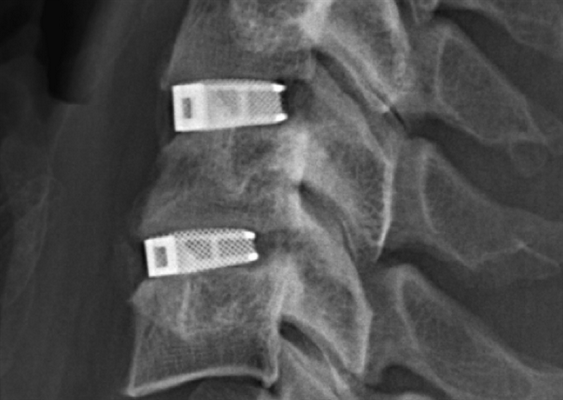

Кейджы межпозвоночных дисков поясничного отдела.

В преобладающем количестве подобные операции заключаются в достижении полного обездвиживания патологических уровней за счет прочного скрепления двух или более позвонков ригидными конструкциями. Это позволяет позвонкам с течением некоторого времени (от 3 до 6 месяцев) срастись между собой и образовать единый неподвижный костный блок. То есть, на прооперированном поле подвижность между позвонками будет заблокирована, а человек сможет нормально двигаться и ходить, не испытывая при этом боли и прочих неврологических расстройств.

Межтеловой кейдж для фиксации позвонков

Чтобы операция дала наилучший результат, часто используется межтеловой кейдж, который должен отвечать таким требованиям:

- обеспечивать стабильность тел позвонков;

- гарантировать сохранение нормальной высоты межпозвоночных дисков, что позволяет избежать компрессии нервов;

- быть изготовленным со специальным пространством через которое, можно вводить костный цемент, искусственную костнозамещающую крошку или препаратов увеличивающих рост костной ткани ;

- Корригировать и фиксировать боковой (сагиттальный) и передний (фронтальный) баланс позвоночника;

- Удерживать нагрузку которая ложиться на ось позвоночника.

Безусловно, предельно качественное выполнение ТПФ обеспечивается при применении устройств 3-го поколения. Современные имплантируемые кейджи позволяют надежно зафиксировать патологически измененный сегмент позвоночника и устранить болевой синдром, обусловленный его остаточной подвижностью.